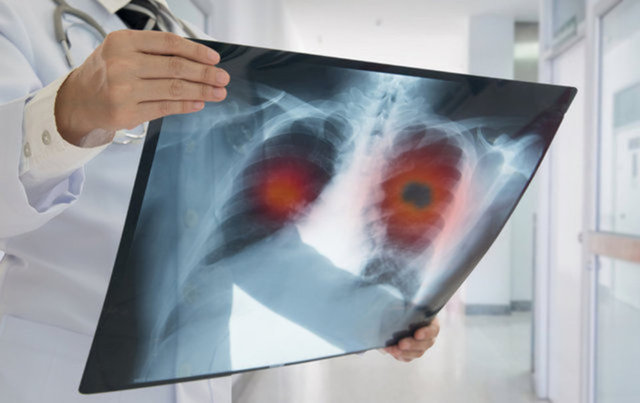

Akciğer kanserinin erken evrede teşhis edilebilmesi için belirtilerde zaman kaybetmeden doktora başvurulması ve yakınması olmasa dahi sigara içen 40 yaş üstü kişilerin yıllık akciğer tomografilerini yaptırmaları çok önemli. Uzmanlar bu konuda sık sık uyarılarda bulunurken, aynı zamanda akciğer kanserinin 8 belirtisi hakkında da bilgilendirme yapıyor. İşte detaylar…